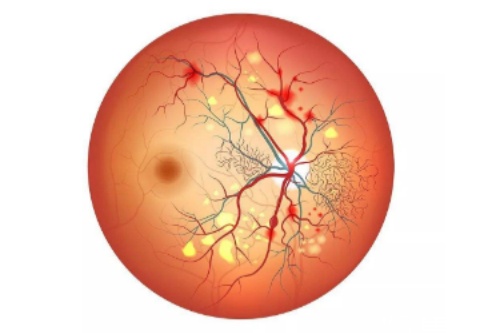

博鳌超级医院采用德国HumanOptics虹膜假体,5D纹理复刻技术误差仅0.02mm。海口国爱主推美国定制虹膜,光敏感度调节功能溢价15%。

手术可行性均达98%,但博鳌医院因使用术中OCT导航,瞳孔居中率比海口高12个百分点。